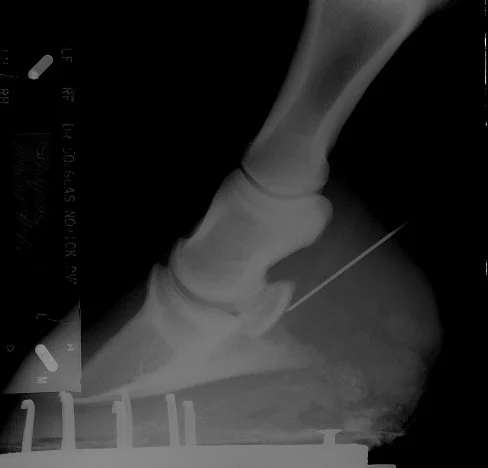

The navicular bursa lies between the navicular bone and the deep flexor tendon as it passes over the navicular bone on its way to inserting into the coffin bone. It as a small fluid filled sac, it helps the deep flexor tendon glide over the back of the navicular bone. Navicular bursa injections are done by placing a 3 inch needle through the back of the hoof into the bursa just behind the navicular bone (after sedating the horse and numbing the area with local anesthesia). The correct placement is confirmed via an x-ray. Then medication similar to that used for joint injections is administered into the bursa.

Figure 1: X-ray of needle placed into the Navicular Bursa.